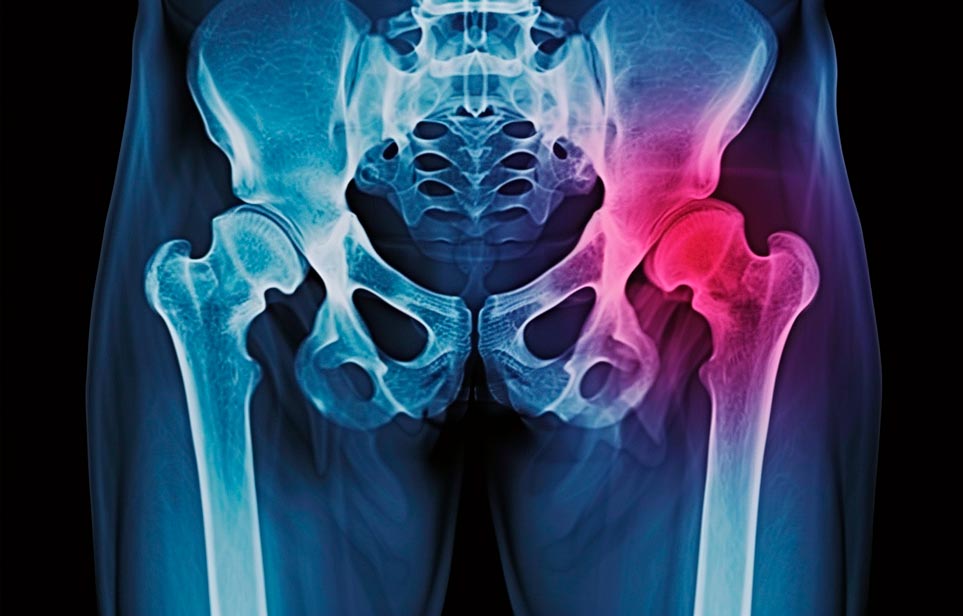

Реабилитация пожилых после перелома шейки бедра в Донецке

Эффективная и профессиональная реабилитация после перелома шейки бедра в Донецке осуществляется по демократичным ценам лучшими специалистами современной медицинской клиники «Заботливые люди» с применением персонального подхода к каждому пожилому человеку с такой тяжёлой травмой бедренной кости ноги. В процессе осуществления такой специализированной услуги все наши пациенты имеют возможность получения качественного и достойного обслуживания, эффективного восстановления. Лучший дом престарелых позаботиться о Вашем близком человеке.

Такая травма в большей части случаев возникает у граждан преклонного возраста. При её появлении на протяжении длительного времени сохраняются болевые и неприятные ощущения в области паха, при которых серьёзно ухудшается качество жизни, возникает множество последствий для его жизни и здоровья.

По какой симптоматике можно определить перелом шейки бедра?

Выявить его можно по возникновению следующей тревожной симптоматики:

- Визуально повреждённая нога сокращается на несколько сантиметром из-за сокращения мышц.

- Стопа выворачивается наружу.

- В лежачем положении человек не может поднять ногу.

При такой симптоматике важно незамедлительно обращаться к специалистам для получения всей необходимой помощи, терапии и восстановления после перелома шейки бедра. Если не оказать помощи старику, то это приведёт к гноению, инвалидности, иным видам осложнений.